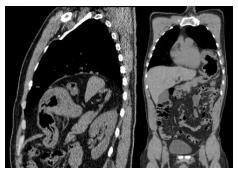

Em relação ao caso apresentado na questão anterior, após estabilização do paciente, ele foi submetido à tomografia de tórax cujo achado mais significativo aparece na seguinte imagem. Com base no exposto, assinale a alternativa correta.

Enunciado 2109885-1